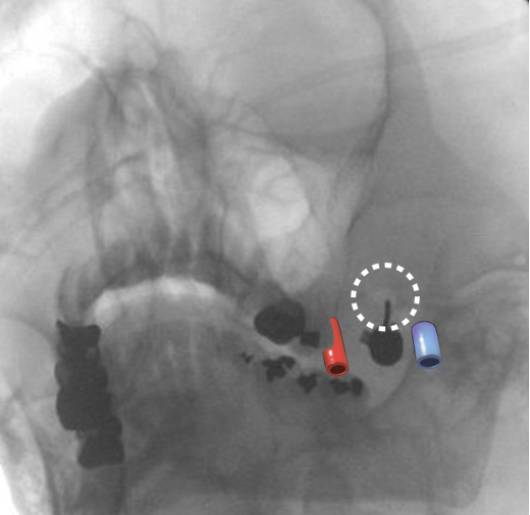

图4. 卵圆孔周围的安全区和危险区。绿色区域代表穿刺针可以反复探查颅底寻找骨孔的安全区。橙色区域代表穿刺针有可能损伤颈内动脉或颈内静脉的危险区。最好是瞄准穿刺针进入前方区域然后向后调整针尖直到穿进骨孔。

图5. 左卵圆孔(虚线内)的X线斜视透射图,方向与穿刺针平行。注意颈内静脉(蓝)和颈内动脉(红)与卵圆孔之间大概的相对位置。